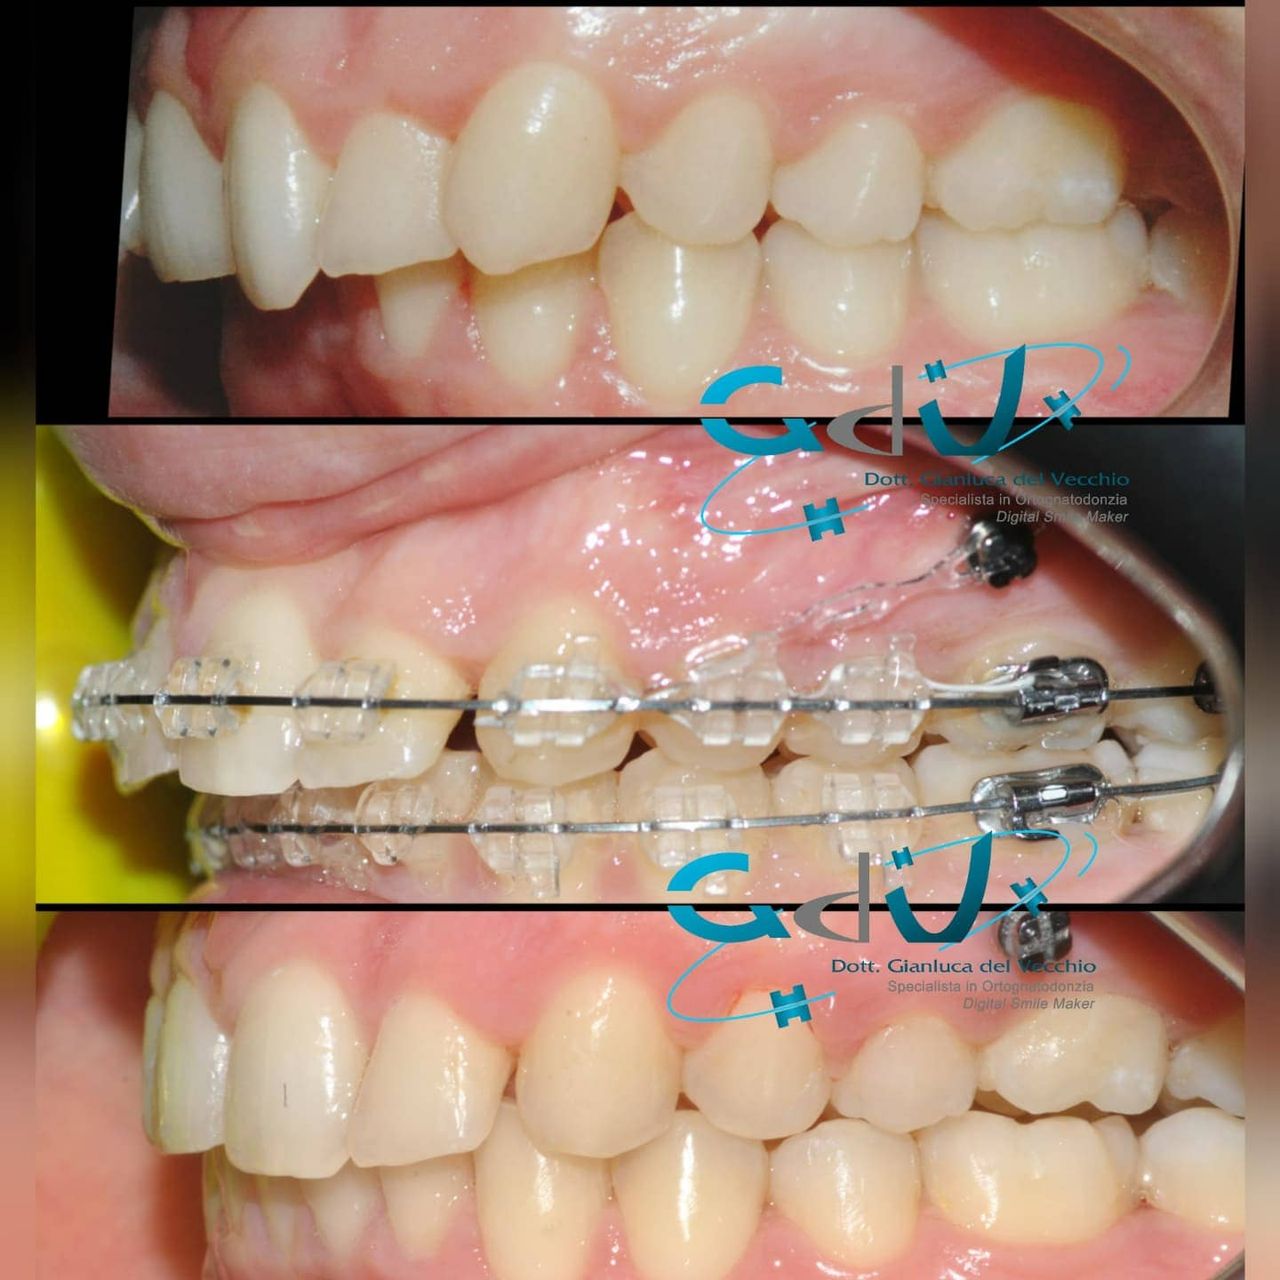

Il dottor Gianluca del Vecchio si occupa esclusivamente di ortognatodonzia, grazie anche alla collaborazione multidisciplinare di una équipe davvero entusiasmante e all’utilizzo di strumenti diagnostici e terapeutici all’avanguardia in ortognatodonzia. Particolare è la sua capacità di condurre i giovani pazienti ad affrontare, nella massima sicurezza emotiva e clinica, qualsiasi eventuale condizione di dolore derivante, ad esempio, da carie o da altre patologie, ma soprattutto di risolvere tutte quelle condizioni di “denti storti”, così spesso causa di disagio psicologico o di fenomeni deprecabili, quale il bullismo.

Il dottore ha acquisito una concezione quanto più pratica e moderna della disciplina e utilizza apparecchietti di diversi colori di tipo mobile e fisso, ma anche terapie sia estetiche che invisibili, fiore all’occhiello di poche realtà in Italia. Per terapie estetiche e invisibili si intendono quelle in grado di spostare i denti, senza che traspaia nulla dalla bocca o con stelline e fili bianchi, esattamente come i denti del paziente.

Ma ancora di più l’équipe è in grado di offrire un servizio davvero unico: la tecnica dei retainer attivi. Questa consiste in fili o bottoni che si incollano dietro i denti e che, quindi, nascondono completamente la terapia. Questo tipo di prestazioni aiuta a superare la grande difficoltà psicologica, che spesso si insinua anche negli adulti, di dover spostare i propri denti per un sorriso perfetto: si consideri che tale difficoltà non viene affrontata, il più delle volte, proprio per l’imbarazzo che una apparecchiatura ortodontica genera in chi la usa. Queste tecniche, insieme alle mascherine invisalign invisibili di cui è provider ufficiale e agli attacchi in ceramica, sono tutte quotidianamente utilizzate presso i nostri reparti, in cui è possibile associarle in un discorso multidisciplinare a tutte le altre esigenze della odontoiatria classica.